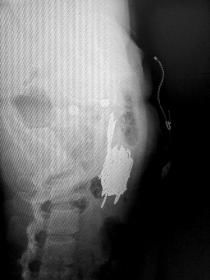

5月13日上午,42歲的曲穎(化名)躺在省直中醫(yī)院普外科的病床上。11日晚上,其因腹痛被路人發(fā)現(xiàn)后撥打120,送往醫(yī)院救治。X光片顯示,其中下腹部橫亙著一捆剪刀,曲穎稱自己為了躲避被抓,便吞下了這些剪刀,大概有10把。

曲穎的x光片顯示,她的體內(nèi)有一捆剪刀。 記者杜方江攝

x光片顯示,一捆剪刀清晰可見。 《長株潭報》記者杜方江攝

剪刀長約12厘米,需手術(shù)取出

當(dāng)天晚上,省直中醫(yī)院急診科對曲穎進(jìn)行了搶救,隨后送往普外科住院治療,從X光片可見一捆剪刀橫亙在其中下腹部,剪刀長近12厘米。醫(yī)生診斷腹部腸管少量積氣,未見明顯液氣平面和腸管擴(kuò)張。曲穎身無分文,普外科醫(yī)生為她進(jìn)行輸液治療。